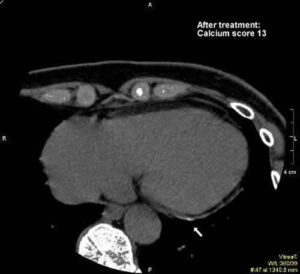

Eventi coronarici acuti: conoscere il grado di calcificazione delle placche nelle arterie

Il grado di calcificazione delle placche nelle arterie del cuore può utilimente essere integrato tra i fattori di rischio più...